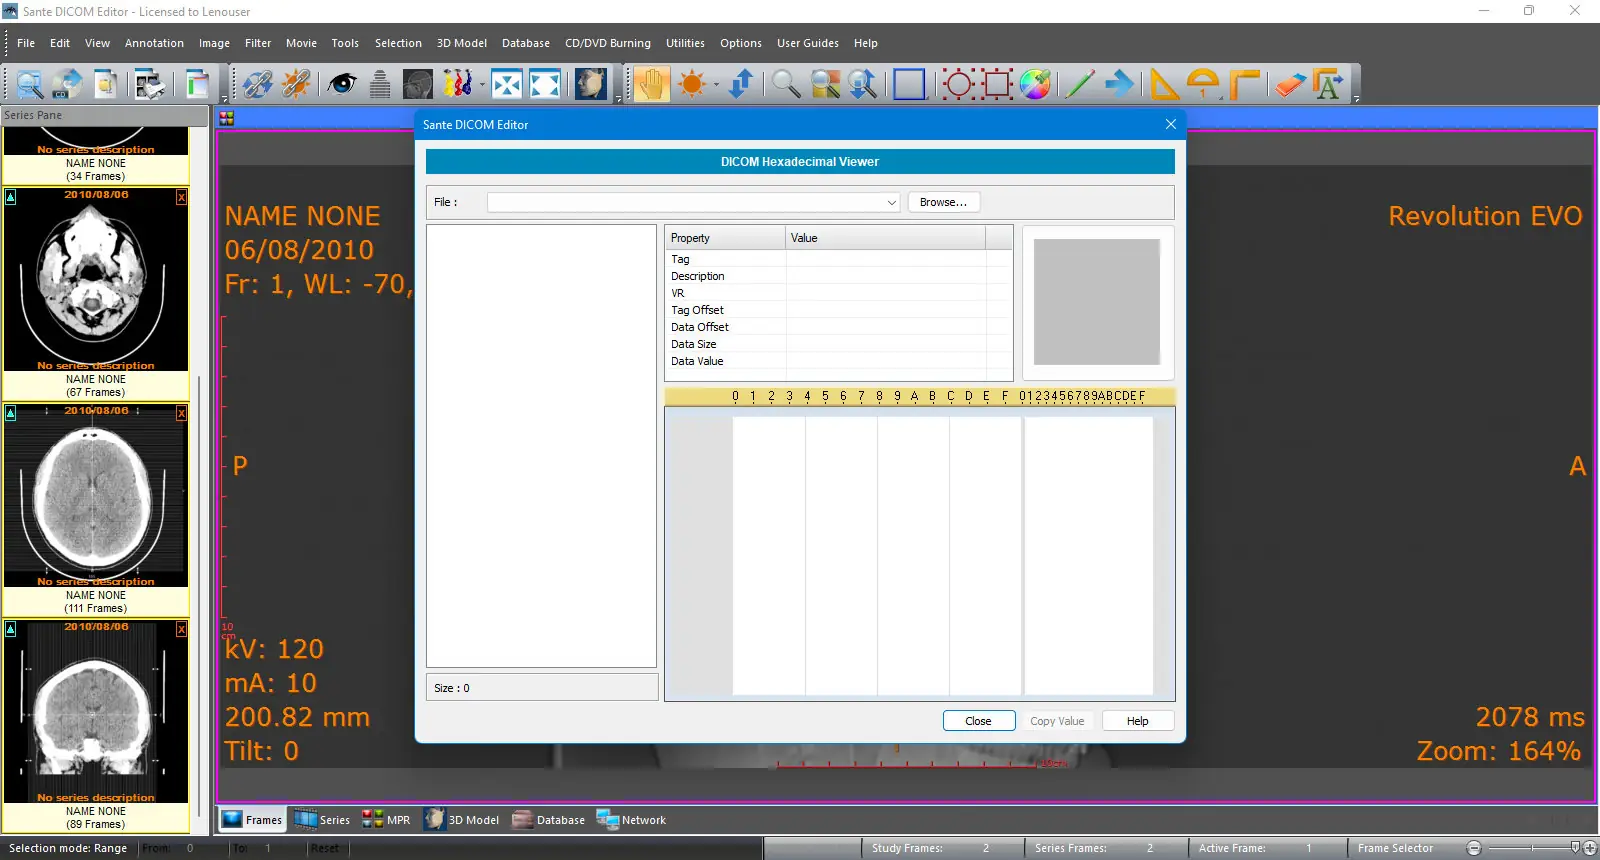

Интерфейс программы выполнен в классическом стиле Windows, что обеспечивает интуитивно понятное управление даже для пользователей без технического опыта. После установки можно импортировать DICOM-файлы напрямую с носителей, с сетевых устройств или через подключение к PACS-серверу. Редактирование атрибутов, включая вложенные последовательности, осуществляется через встроенный редактор заголовков с возможностью применения шаблонов для массовых изменений.

Программа представляет собой комплексное решение для обработки медицинских изображений, сочетающее в себе возможности мощной рабочей станции, поддерживающей2D и3D визуализацию. Она позволяет не только просматривать и редактировать файлы DICOM, но и выполнять сложные операции, такие как создание трёхмерных моделей методами isosurface, объёмного рендеринга и проекции максимальной интенсивности. Поддержка всех распространённых кодировок делает её пригодной для использования в международных медицинских учреждениях, включая те, где применяются кириллица, арабский или азиатские символы.